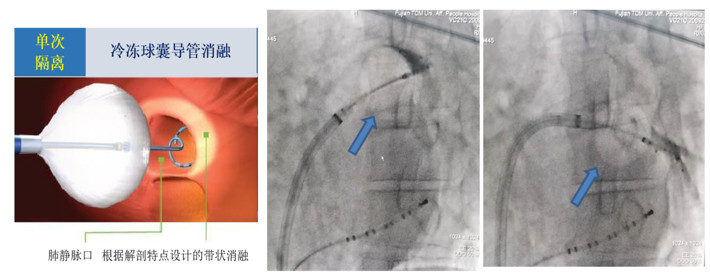

房顫冷凍球囊導(dǎo)管消融